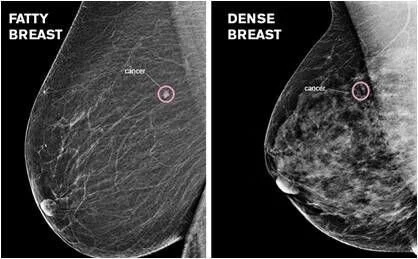

Limitations of mammogram: DID YOU KNOW MAMMOGRAM MAY MISS TUMOR ?

Dense Breast: A false-negative mammogram looks normal even though Breast cancer is present. Women with dense breast have more false-negative results. Breast tissue is composed of milk glands, milk ducts and supportive tissue (dense breast tissue), and fatty tissue (non-dense breast tissue). Mammogram determines the ratio of non-dense tissue to dense tissue and assigns a level of breast density. Dense breast tissue makes it more difficult to interpret a mammogram, since cancer and dense breast tissue both appear white on a mammogram. On a mammogram, non-dense breast tissue appears dark and transparent. Dense breast tissue appears as a solid white area on a mammogram, which makes it difficult to see through.